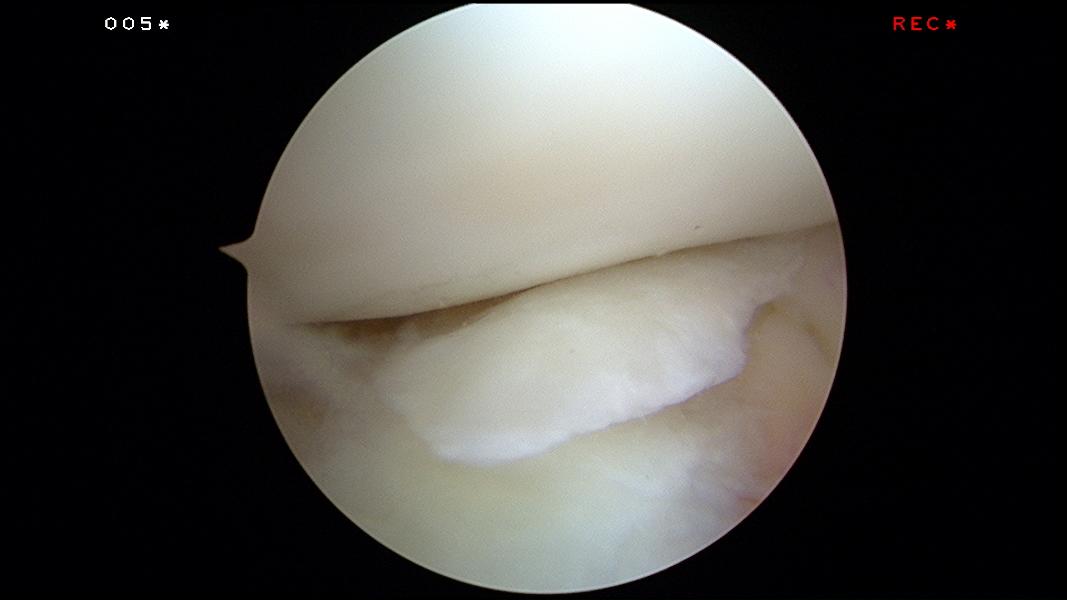

This is how it looks like during arthroscopy:

The torn cartilage was found floating inside the knee. Sometimes it cannot be found.